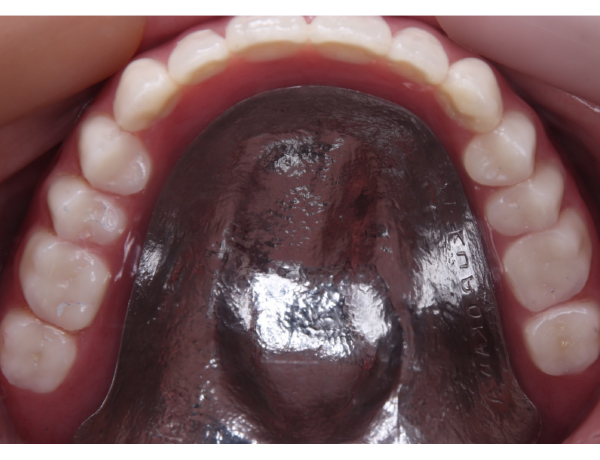

上あご

赤丸の部分にこれでもかってくらい大きな骨の隆起があります。噛む力がかなり強そうです。

1. 噛む力が非常に強い お口の中には骨隆起が認められました。赤丸で示している部分が、口蓋隆起と呼ばれる骨の盛り上がりです。このような骨隆起がある場合、噛む力が一点に集中しやすく、入れ歯に通常以上の負担がかかります。

お口の中に入っても、金属の部分がだいぶ広くとってあるのが分かるかと思います。口蓋隆起と言われる骨の部分が当たると痛みが出るので、少しその部分はリリーフして隙間を与える工夫もしています。